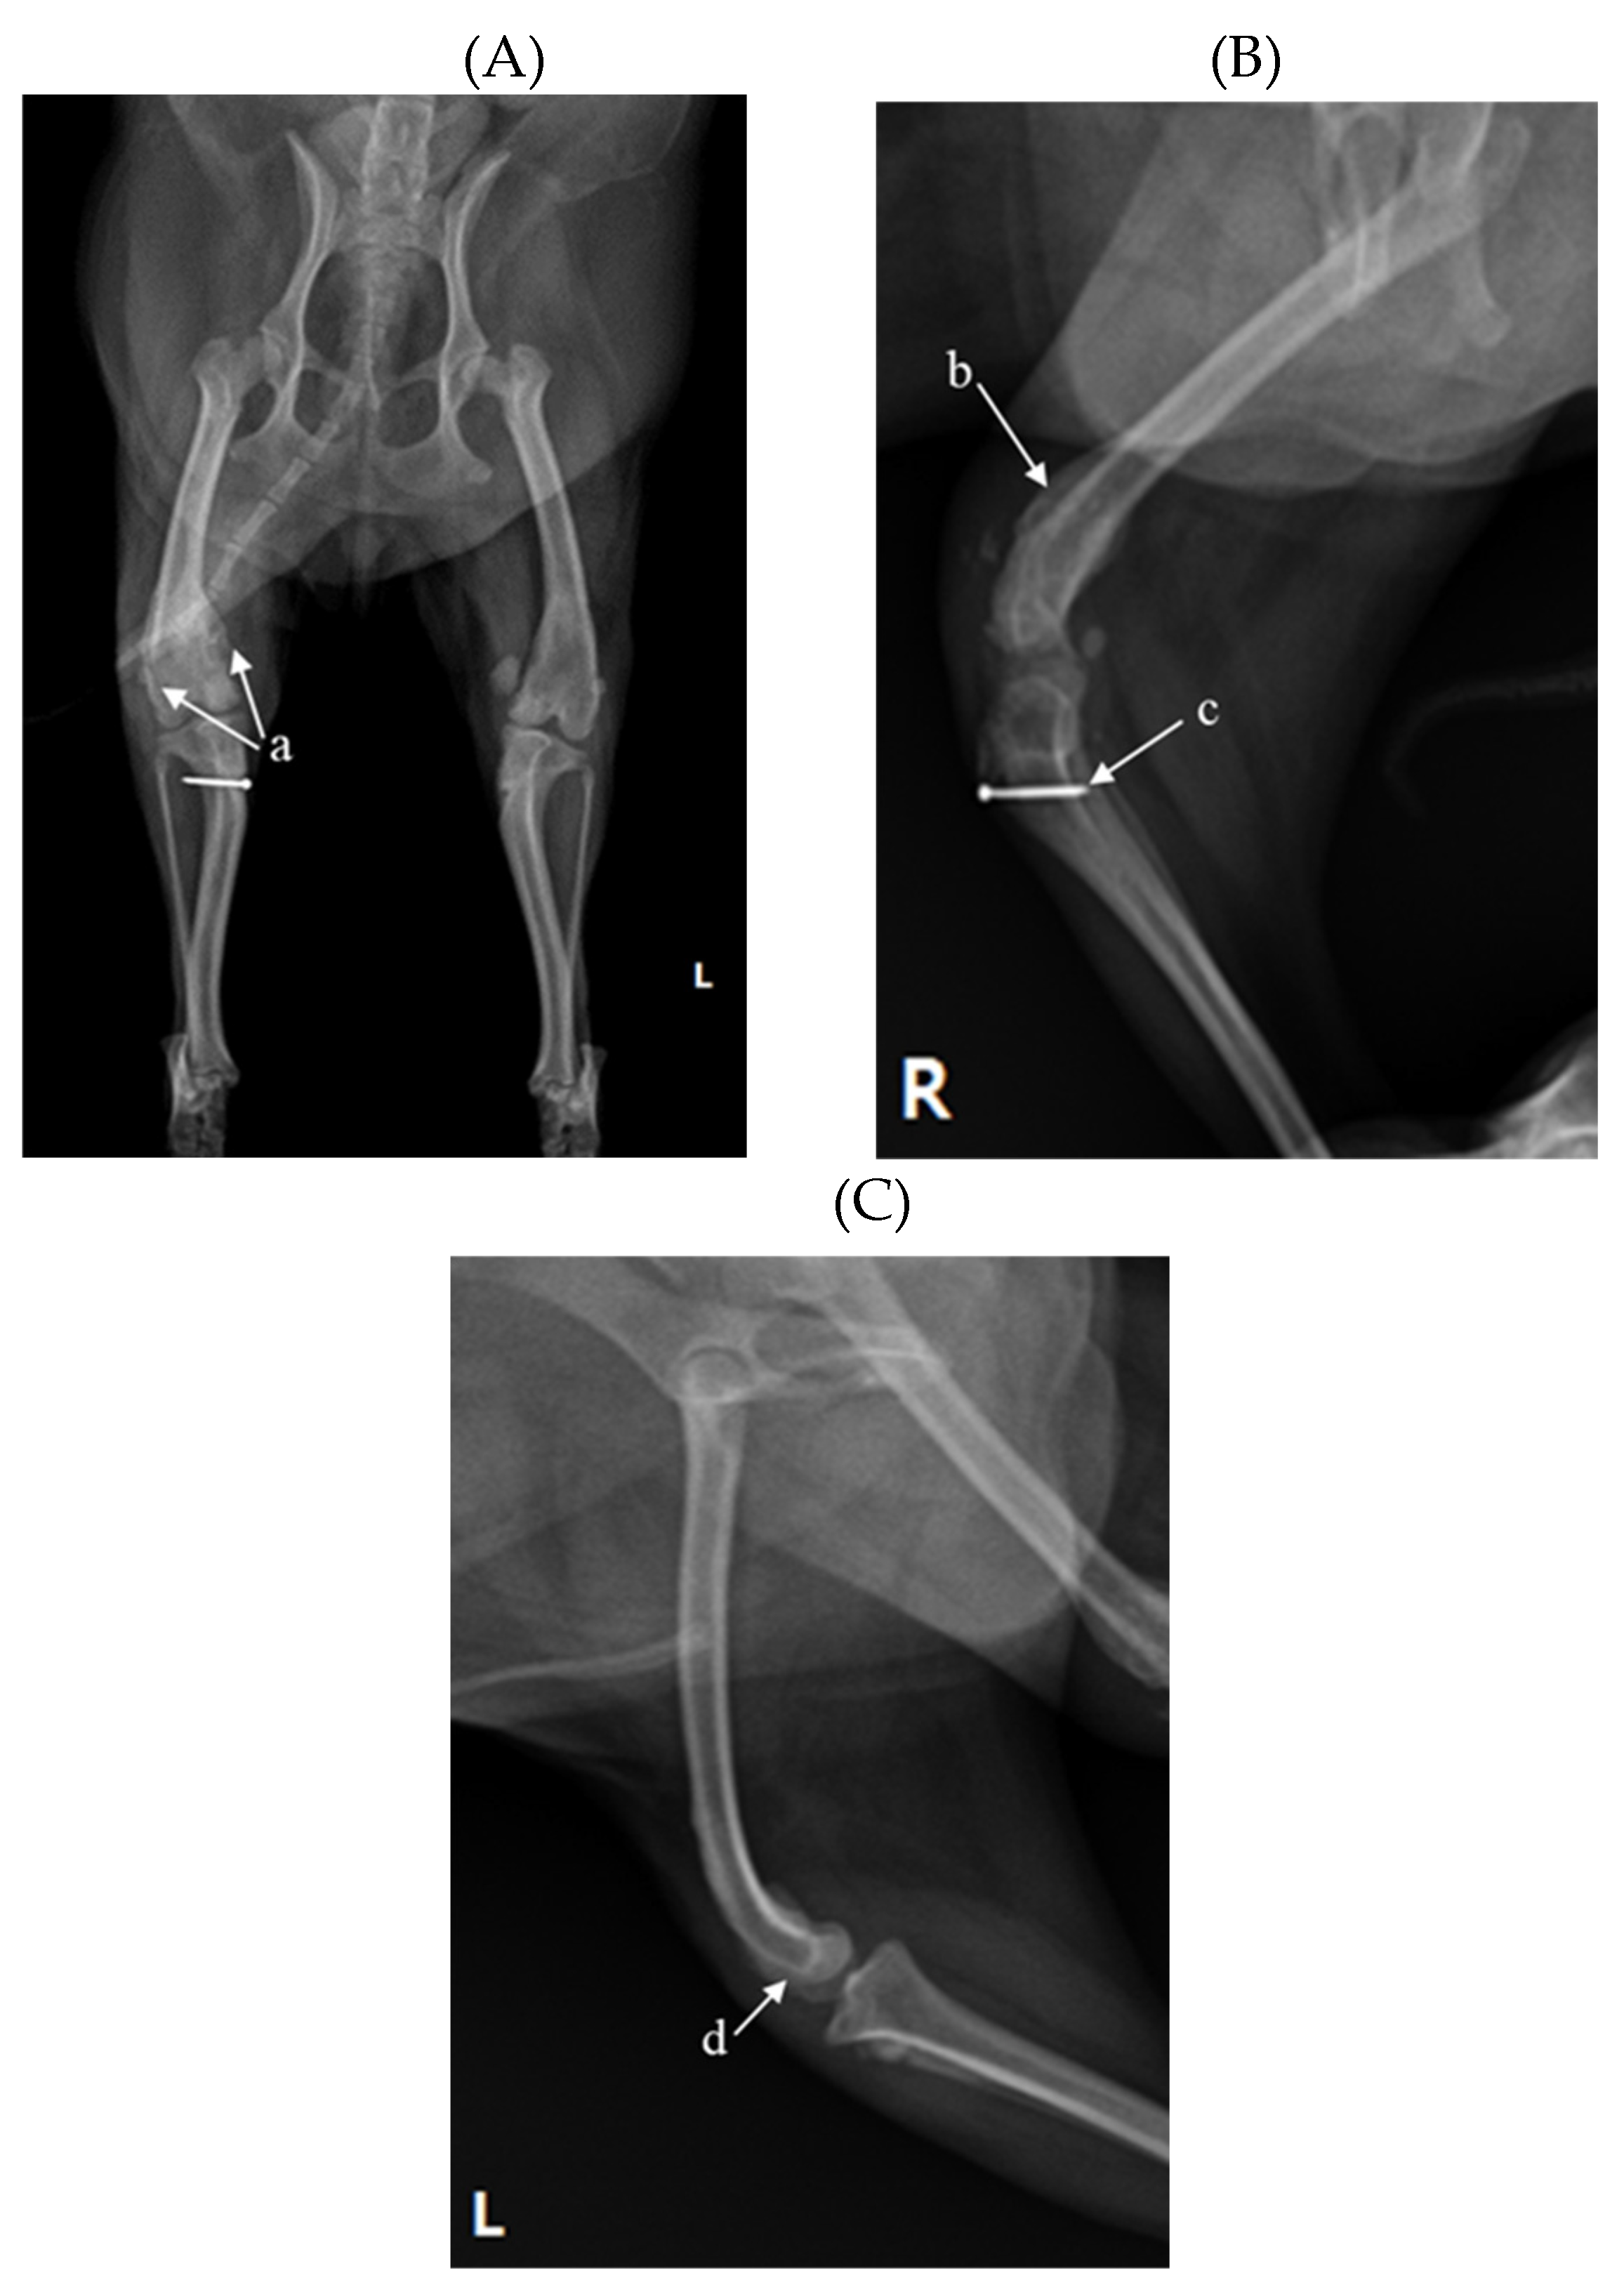

According to X-ray imaging, the screw fixating the bone fragment to the tibial tubercle in the right hind limb remained, and the patella was not recognized in the radiography view, which was consistent with results following palpation (Figure 1A and B). Bone pro-liferation appeared and edema was observed around the stifle joint (Figure 1A and B). Se-vere MPL, periostitis and edema around the stifle joint in the left hind limb were observed (Figure 1A and C). Following a physical examination, neutrophils were reported as slightly increased at 11.71 μL (78.2%), suggesting that inflammatory responses were in progress (Table 1).

Figure 1. A 2-year-old Pomeranian dog had chronic weight-bearing lameness of the stifle joints in both hind limbs. (A) Craniocaudal radiographic views of the stifle joints of the dog. (B) Lateral radiographic views of the right stifle joints. (C) Medial radiographic views of the left stifle joints. a: osteophyte, b: periostitis, c: residual screw for tibial tuberosity transposition, d: periostitis, R: right, L: left.